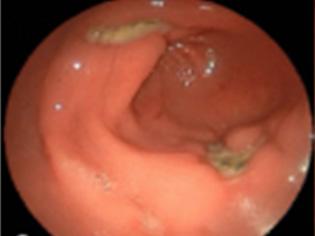

En casos de estreptococo bovis se asocia con cáncer o pólipo en el colon.

El flujo turbulento daña el endotelio de las válvulas activando la hemostasia y se forman vegetaciones asépticas formadas por plaquetas y fibrina (trombo estéril). Luego, estas se contaminan debido a una bacteriemia por un foco séptico, formándose una verruga bacteriana (vegetación séptica), la cual puede destruir la válvula (rotura de cuerdas tendinosas, músculo papilar) y formar abscesos, produciendo la clínica cardiaca; los émbolos sépticos que pasan a la circulación sistémica dan lugar a la clínica extracardiaca (en casos de ADVP, predominan los émbolos pulmonares).

La triada clínica es fiebre (95 %), soplo de regurgitación (85 %) y esplenomegalia (30 %) . Además, podría haber clínica extracardiaca producto de los émbolos sépticos al territorio de la arteria cerebral media, como hemiparesia por un ictus isquémico en pacientes jóvenes o manifestaciones embólicas pulmonares (tos, disnea y hemoptisis), que son más frecuentes en los pacientes ADVP.

Masa oscilante sugerente de verruga o absceso o dehiscencia de prótesis.